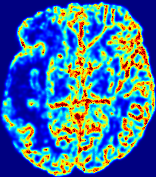

LesionRefer to captionRefer to captionRefer to captionRefer to captionRefer to captionRefer to caption𝐕rgbsubscript𝐕𝑟𝑔𝑏{\bf{V}}_{rgb}Refer to captionRefer to captionRefer to captionRefer to captionRefer to captionRefer to caption𝐕2subscriptnorm𝐕2{\|\bf{V}}\|_{2}Refer to captionRefer to captionRefer to captionRefer to captionRefer to captionRefer to captionRefer to caption3.53.53.52.82.82.82.12.12.11.41.41.40.70.70.70.00.00.0(mm/s)𝑚𝑚𝑠(mm/s)D𝐷DRefer to captionRefer to captionRefer to captionRefer to captionRefer to captionRefer to captionRefer to caption0.0200.0200.0200.0160.0160.0160.0120.0120.0120.0080.0080.0080.0040.0040.0040.0000.0000.000(mm2/s)𝑚superscript𝑚2𝑠(mm^{2}/s)Slice #1Slice #2Slice #3Slice #4Slice #5Slice #6

Figure 4: PIANO feature maps for another patient in the ISLES 2017 training set, where the lesion is located in the right hemisphere. Top row: segmented stroke lesion region (white) on different slices. The corresponding slices for the PIANO feature maps are shown in the following rows.

For a better insight into an estimated velocity field 𝐕𝐕{\bf{V}} and diffusion field 𝐃𝐃{\bf{D}}, we compute the following maps: (1) 𝐕rgbsubscript𝐕𝑟𝑔𝑏{\bf{V}}_{rgb}: Color-coded orientation map of 𝐕=(Vx,Vy,Vz)T𝐕superscriptsuperscript𝑉𝑥superscript𝑉𝑦superscript𝑉𝑧𝑇{\bf{V}}=(V^{x},V^{y},V^{z})^{T}, obtained by normalizing 𝐕𝐕{\bf{V}} to unit length and mapping its 3 components to red, green, blue respectively; (2) 𝐕2subscriptnorm𝐕2\|{\bf{V}}\|_{2}: 222 norm of 𝐕𝐕{\bf{V}}; (3) D𝐷D: scalar field in Eq. 5.

Fig. 3 and Fig. 4 show the PIANO feature maps estimated from two ISLES 2017 patients: all are highly consistent with the lesion in both cases. Details of the blood flow trajectories are revealed in 𝐕rgbsubscript𝐕𝑟𝑔𝑏{\bf{V}}_{rgb} by the ridged patterns and the sharp changes of colors in the unaffected (right) hemisphere, while the flat patterns appearing within the lesion provide little directional information about the velocity and indicate low velocity magnitudes. Velocity magnitudes are more directly visualized via 𝐕2subscriptnorm𝐕2\|{\bf{V}}\|_{2}, from which one can easily locate the lesion where 𝐕2subscriptnorm𝐕2\|{\bf{V}}\|_{2} is low. D𝐷D also indicates lower diffusion values in the lesion, though with less contrast potentially due to the fact that it captures the accumulated effect of CA diffusion at the voxel-level.